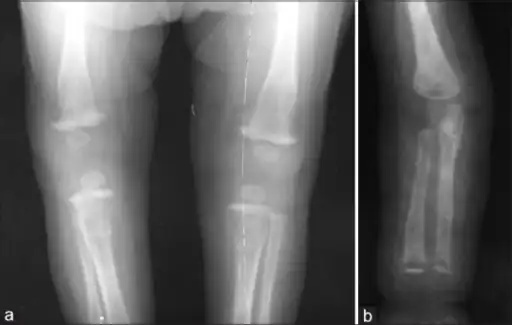

Wimberger corner sign; X-rays of (a) lower limbs (AP view) and (b) upper limbs (AP view) showing resolution of metaphyseal erosions and periosteal reaction -

a) X-ray of the lower limb (AP view) showing proximal tibial metaphyseal erosions along with periosteal reaction and (b) X-ray of the upper limb (AP view) showing distal tibial and fibular metaphyseal erosions with periosteal reaction -